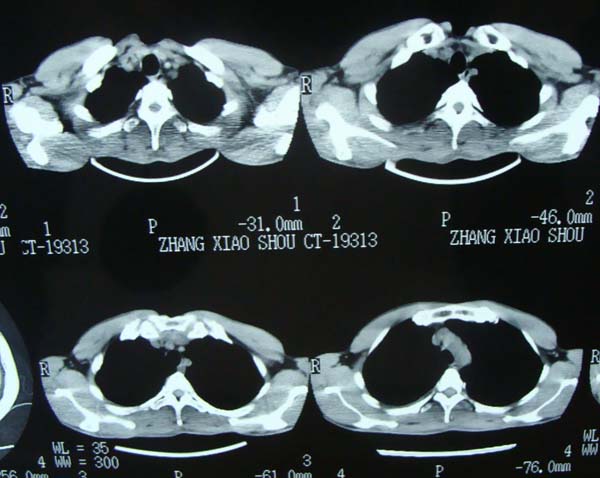

标题: CT15132:男,26岁。建筑混凝土工人。发热。咳。 [打印本页]

标题: CT15132:男,26岁。建筑混凝土工人。发热。咳。

右肺继发型肺结核,右侧胸腔积液、胸膜肥厚粘连。

右肺继发型肺结核,右侧胸腔积液。

继发结核并胸水

胸膜肥厚

年轻男性,右肺多形性病灶伴右侧胸腔积液,考虑结核